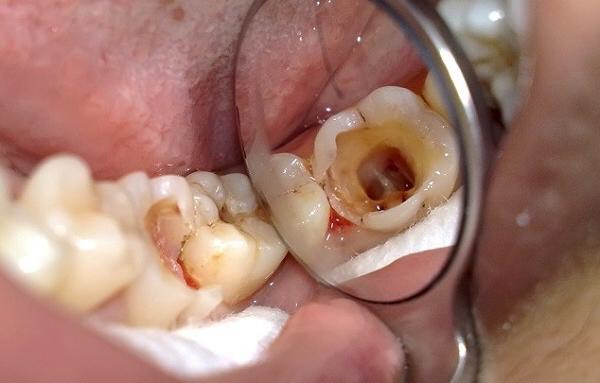

4.2. Chẩn đoán sâu răng giai đoạn hình thành lỗ sâu

- Tổn thương mất mô cứng của răng có thể rất nhỏ, chỉ xác định được khi thăm khám với dụng cụ chuyên biệt của các bác sĩ nha khoa hoặc biểu hiện rõ hình ảnh lỗ sâu với các đặc điểm sau:

- Vị trí: Mặt nhai các răng hàm sữa, mặt gần - xa, mặt ngoài và mặt trong các răng.

- Kích thước: có thể nhỏ giới hạn trong một mặt răng hoặc lan rộng sang hai/ ba mặt.

- Độ sâu: Có thể chỉ tổn thương lớp men răng hoặc tổn thương đến lớp ngà răng.

- Đáy: Có thể mềm có nhiều ngà mủn hoặc đáy cứng tùy vào giai đoạn tiến triển của sâu răng

+ Mầu sắc: Màu men ngà răng hoặc màu vàng nâu, đen.